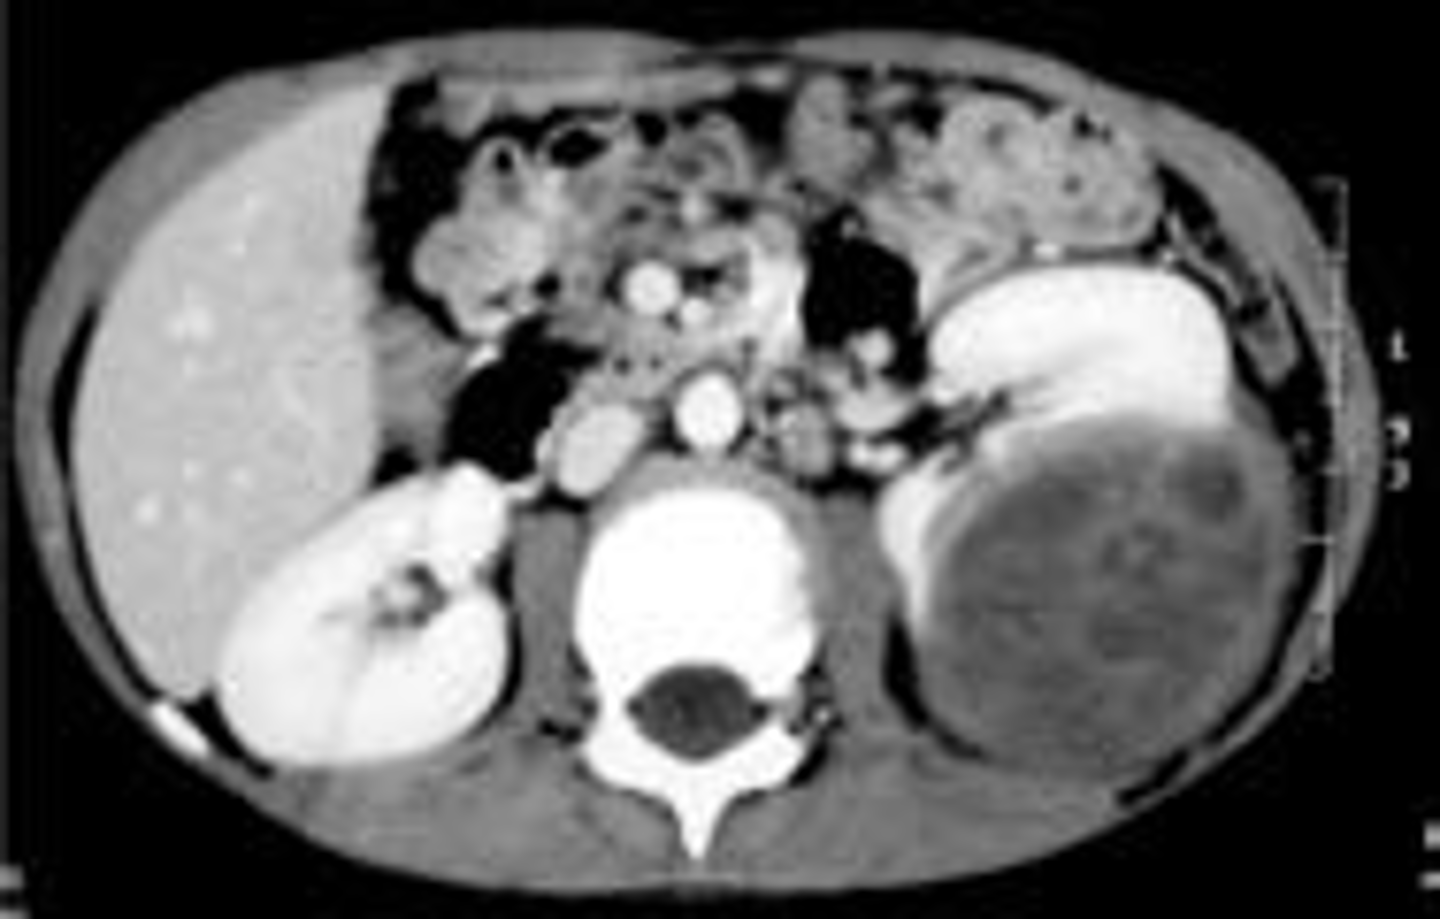

What is the best initial diagnostic test for autosomal dominant PCKD? What is the best overall?

Initial: renal US

Overall: MRI

When does autosomal dominant polycystic kidney disease (PCKD) typically present? What are some common s/sxs?

Childhood or adulthood; early-onset HTN, mild polyuria, hematuria, episodic flank pain, nephrolithiasis, UTI, hepatic cysts, & intracranial aneurysms